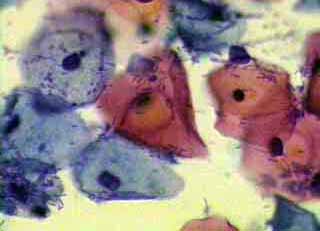

κυτταρολογικών επιχρισμάτων κατά Papanicoloau και η συσχέτιση τους με το ιστορικό

Το ενδιαφέρον του κλινικού γυναικολόγου στο πόρισμα του κυτταρολογικού επιχρίσματος του τραχήλου της μήτρας, περιορίζεται συνήθως στο συμπέρασμα του, σχετικά με την ύπαρξη κάποιας δυσπλασίας ή έστω φλεγμονής, στην περιοχή.

Ωστόσο ακόμη και το λεγόμενο ‘’φυσιολογικό’’ επίχρισμα, μπορεί να μας δώσει μία επί πλέον αξιόλογη πληροφόρηση, αν τα ευρήματα του ενταχθούν σωστά από τον κλινικό γιατρό, τόσο στην χρονική συγκυρία, όσο και στο ιστορικό, ή στα κλινικά, κολποσκοπικά και υπερηχογραφικά ευρήματα.

Η γενικότερη γυναικολογική οπτική γωνία, στην ερμηνεία ενός κυτταρολογικού πορίσματος, είναι αρκετά σημαντική για την αξιολόγηση άλλων προβλημάτων, πέραν των δυσπλασιών.

Οι εικόνες και τα πορίσματα που επιδεικνύονται, είναι τυχαία ευρήματα ενός απογευματινού ιατρείου.